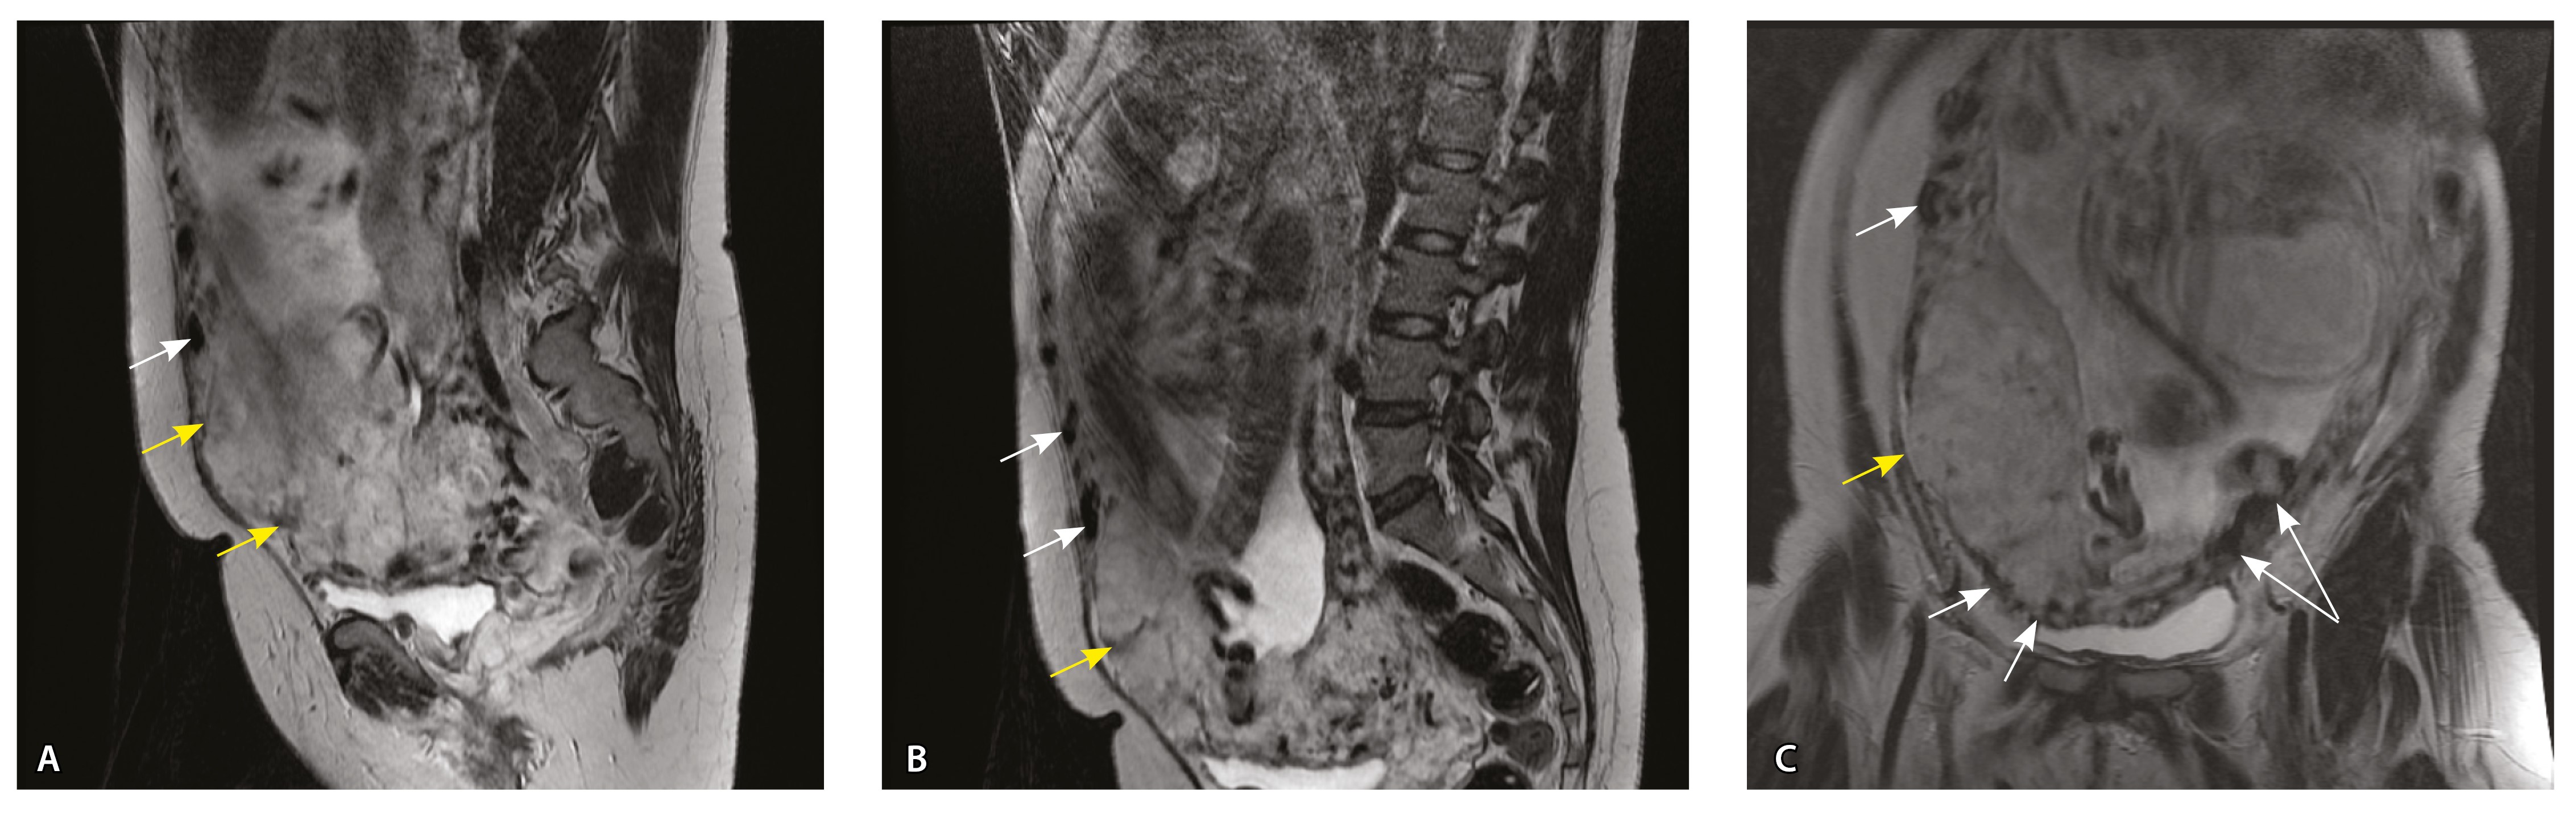

Сосуды 3-го типа. Внутриматочная гиперваскуляризация с дефицитом толщины миометрия, преимущественно сосуды срединного слоя, аналог pl. increta PAS 2, гестационная перестройка радиальных артерий (рис. 7).

Рис. 7. Беременность 34 недели, pl. increta, PAS 2 по FIGO. На магнитно-резонансных томограммах в режиме Т2-взвешенного изображения в сагиттальной (A, Б) и фронтальной (В) плоскостях определяется внутриматочная гиперваскуляризация с наличием многочисленных сливающихся сосудов в толще стенки матки, в области плацентарной площадки (белые стрелки); в нижнем маточном сегменте – выраженное истончение стенки матки, рубца от кесарева сечения с формированием маточной грыжи (желтые стрелки)

Рис. 10. Беременность 33 недели, pl. percreta, PAS 3a по FIGO. На магнитно-резонансных томограммах в режиме Т2-взвешенного изображения в сагиттальной (A) и фронтальной (Б, В) плоскостях определяется внутриматочная гиперваскуляризация (желтые стрелки) и гиперваскуляризация в области выраженно истонченного нижнего маточного сегмента, с наличием многочисленных анастомозирующих сосудов по поверхности матки (белые стрелки); стенка матки в данной области представлена ретроплацентарными сосудами